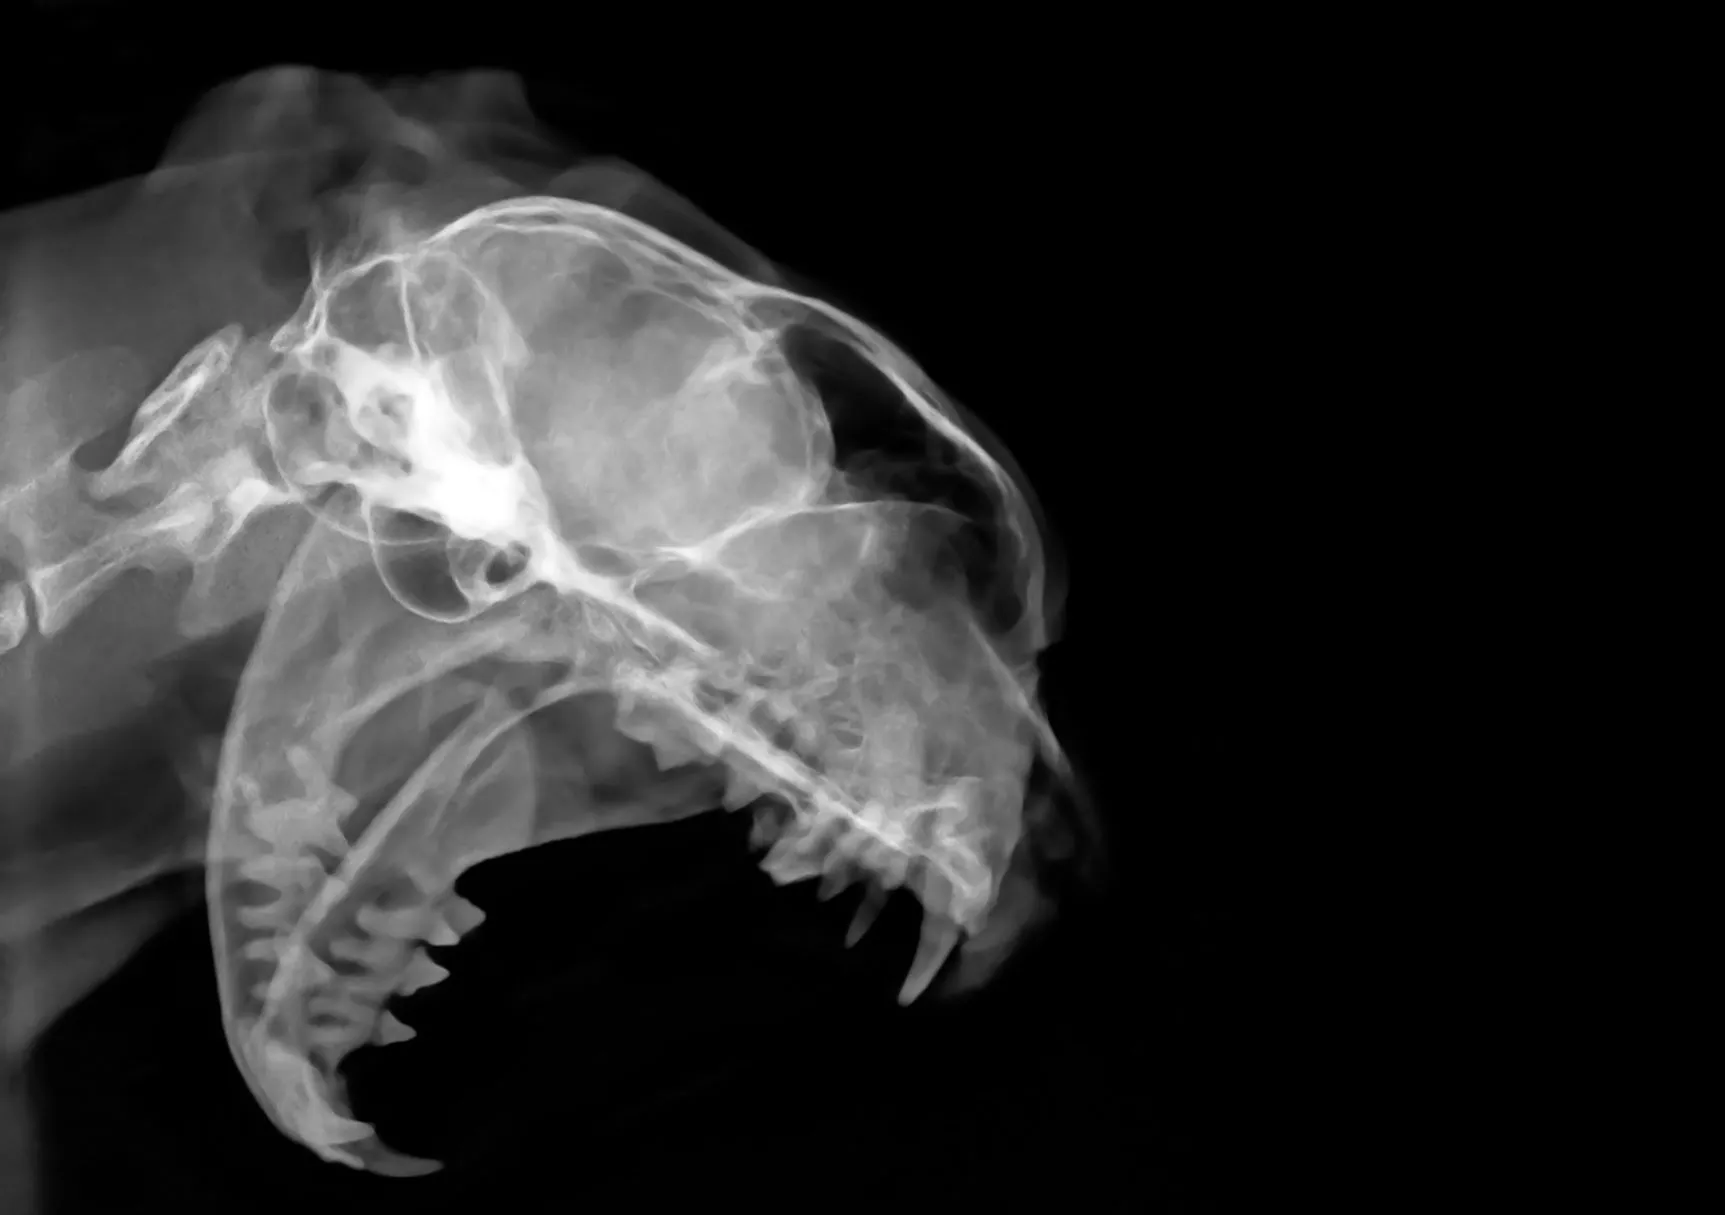

Ein sicherer Nachweis von FORL bei Katzen ist für Tierärzte nicht immer ganz einfach. Um auch die von aussen nicht sichtbaren Gewebe (z. B. Zahnwurzeln) beurteilen zu können, erfordert FORL bildgebende Verfahren wie das dentale Röntgen.

Erst durch den Blick auf das Röntgenbild kann Ihr Tierarzt von aussen gesund erscheinende Zähne als schmerzhafte FORL-Zähne identifizieren.

Röntgenaufnahme eines Katzenkopfes © Ivan Floriani / stock.adobe.com

Um FORL diagnostizieren zu können, muss der Tierarzt eine Röntgenaufnahme machen.